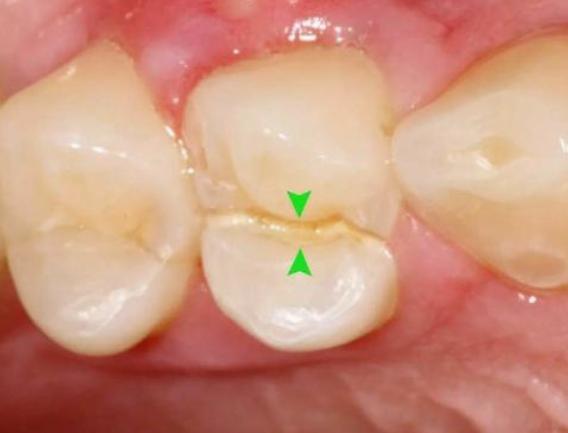

于是抱着侥幸心理,让牙齿在没有“防护衣”的情况下:咬着小坚果,嗑着小瓜子……有一天,“咔”!牙齿劈裂了!

根管治疗是针对牙髓炎或牙髓坏死、根尖病变不能保留活髓的折裂牙,进行治疗的有效方法。

- 牙髓炎:牙髓因细菌感染而发炎。在密封的牙髓腔中,牙髓通常不会被细菌感染。当牙齿因龋齿而开孔时,该孔太深,外部细菌会侵入牙髓腔,从而感染骨髓。

- 牙髓裸露:当牙齿折断并且牙齿的神经暴露时,通常需要进行根管治疗。